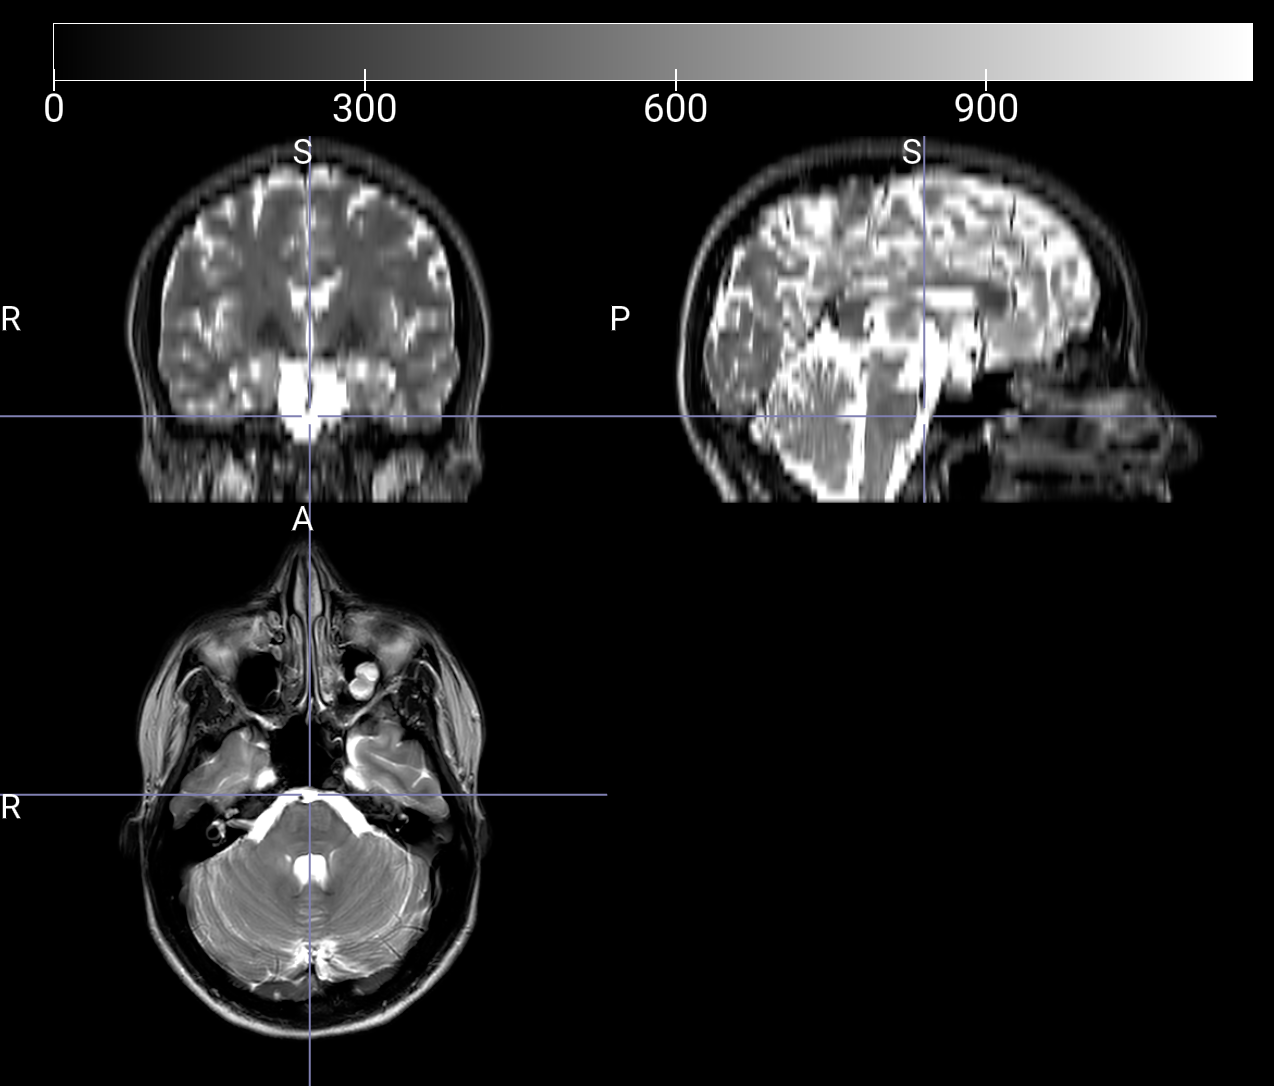

I was wondering if anyone could identify, how to adjust the

settings for loading all volumes? This will predictively enable the

large file images to NOT be downsampled and blurred (see

attachment).